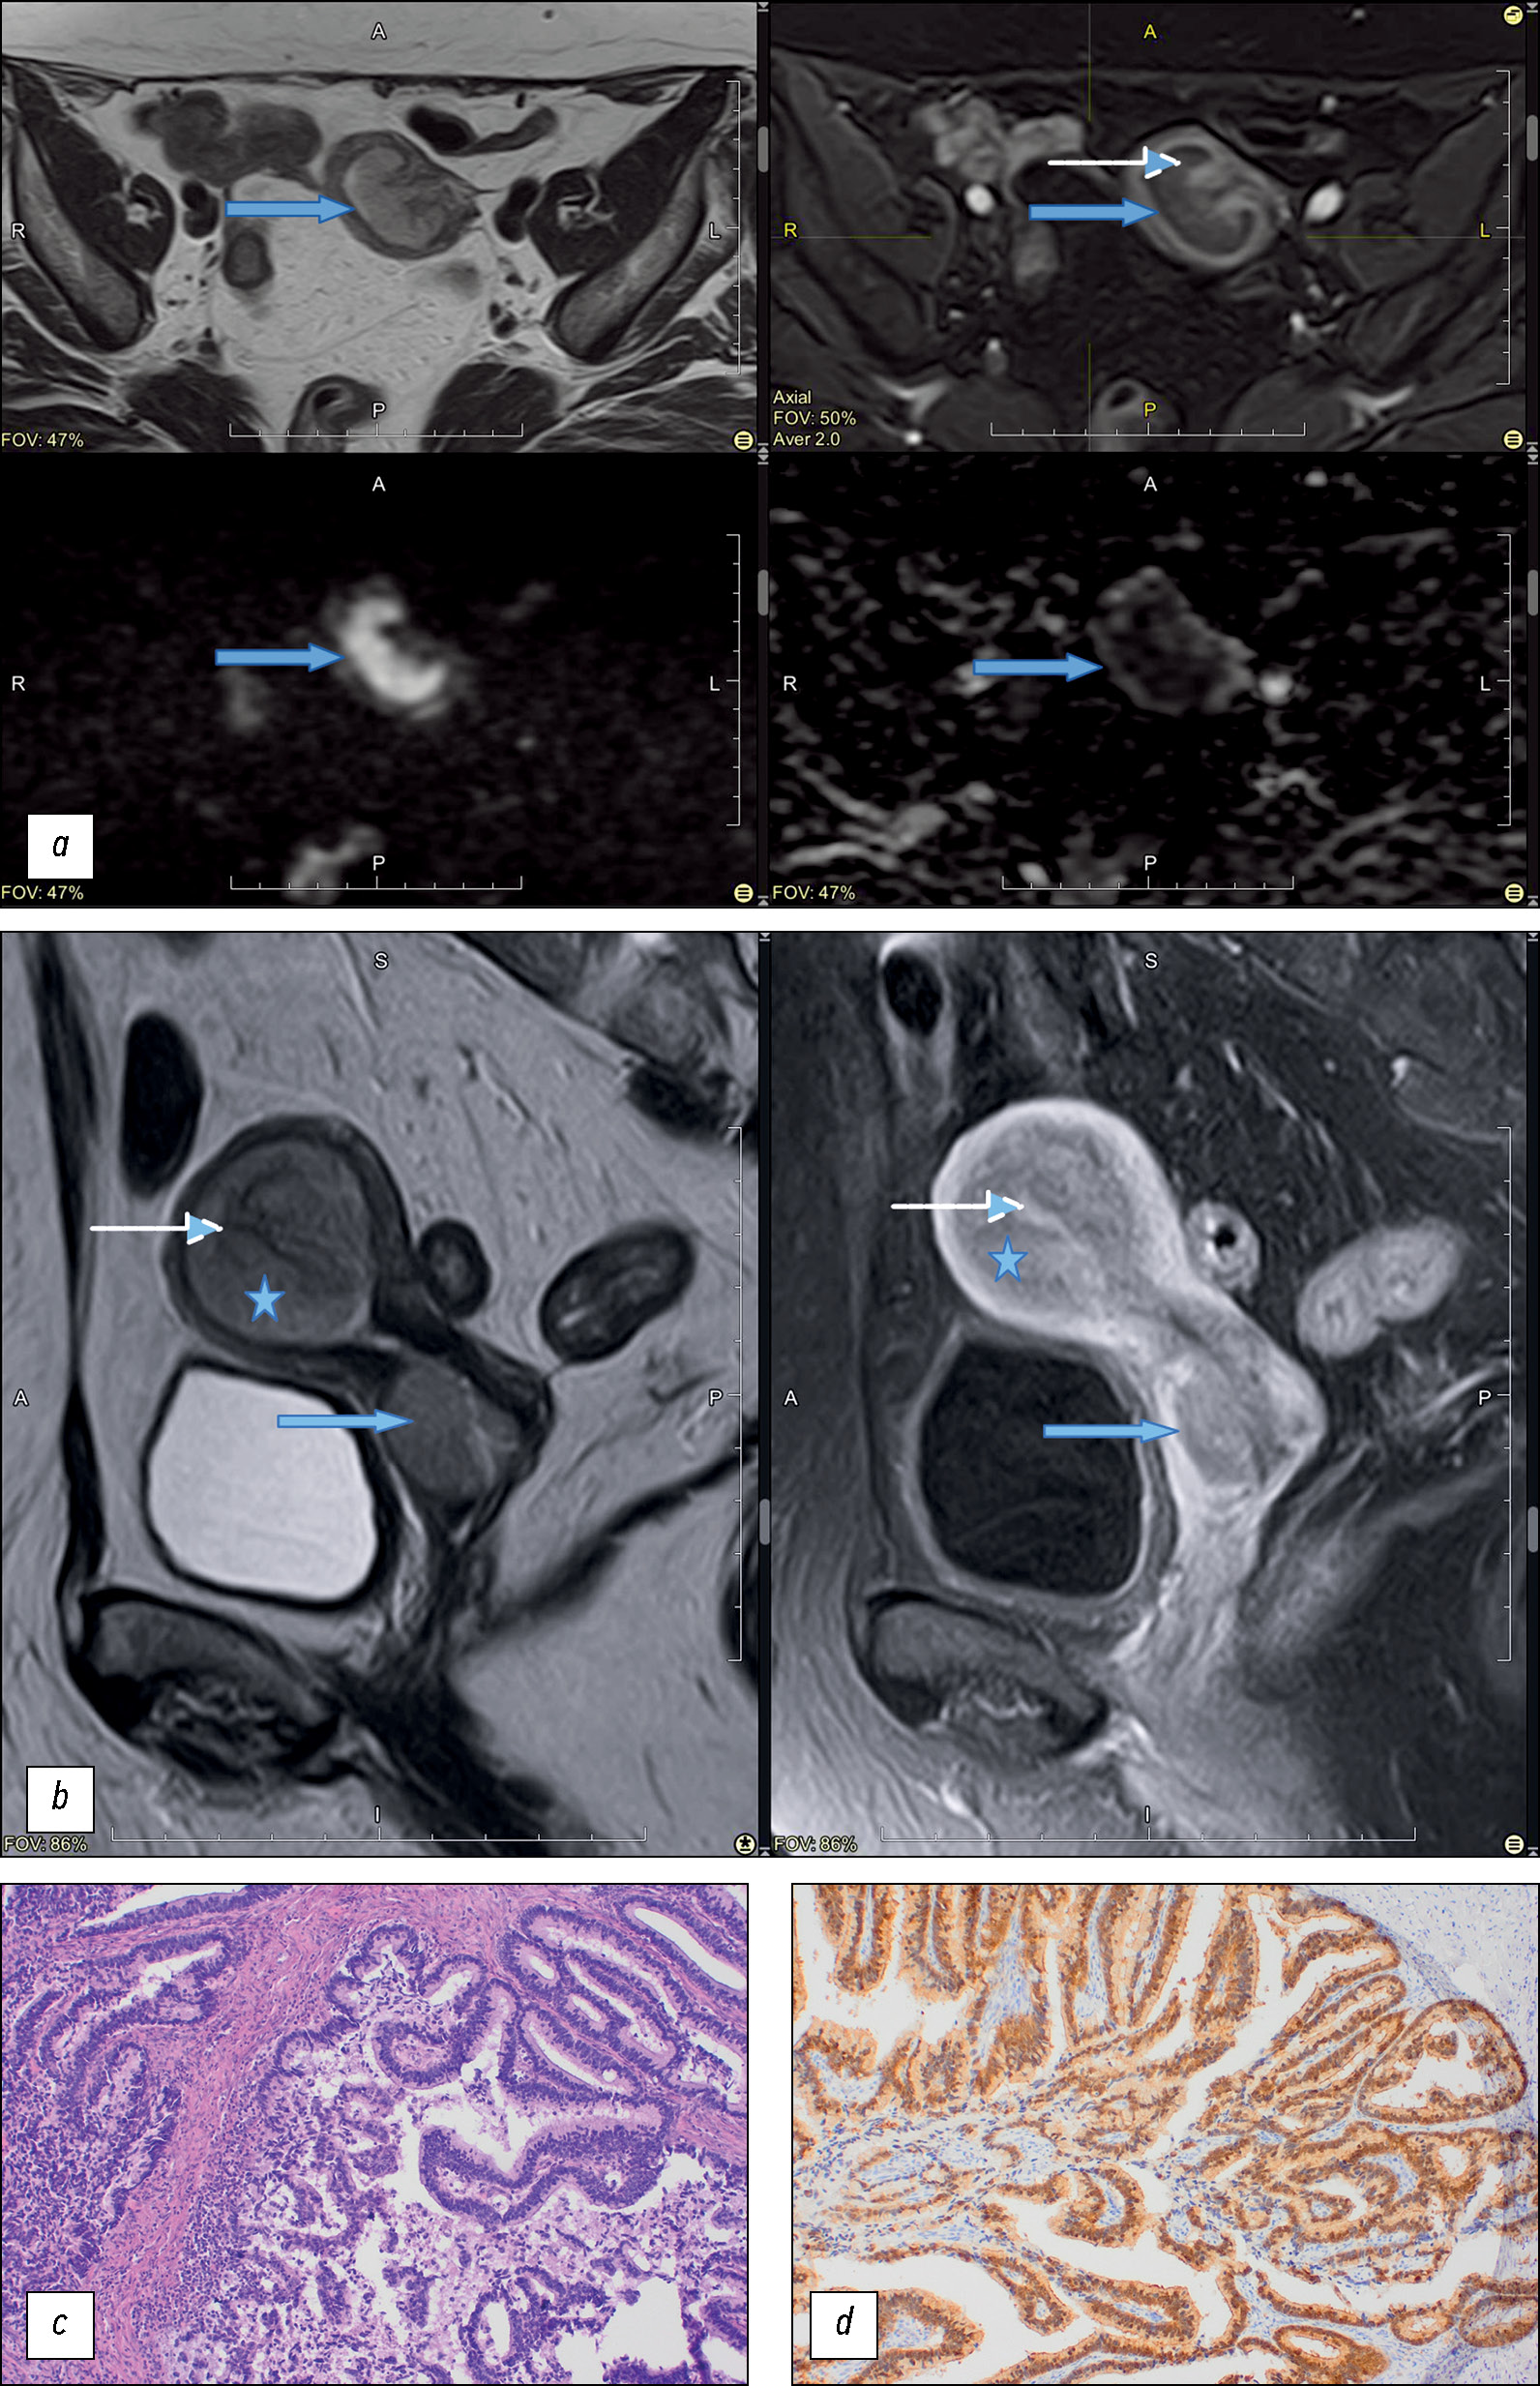

We identified two types of tumor growth in the cervical stroma: the most common were the endophytic type (75%, n = 15), characterized by diffuse enlargement and barrel-shaped cervical transformation (Fig. 3), and exophytic type, which occurred in 25% of cases in the present study (n = 5). Exophytic tumors were most commonly located in the vaginal cervix, with tumor masses prolapsing into the vagina or cervical canal lumen (Fig. 3). The exophytic tumor was represented by different histologic subtypes of CA:

Fig. 3. Сervical adenocarcinoma growth pattern. The upper row of images is T2-weighted images in sagittal plane, the lower one — in axial plane.

Furthermore, endophytic tumors were characterized by different histologic types and differentiation patterns. No correlation was found for the type of tumor growth and its histologic subtype.